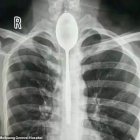

¡Se tragó una cuchara de 20 centímetros y se la retiraron un año después!

El alcohol le jugó una mala pasada a un hombre chino tras perder un reto con sus amigos.